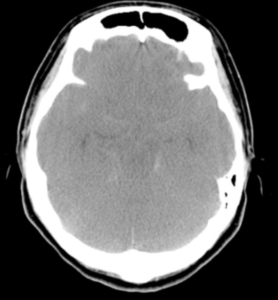

| 検査 | 【画像検査】 ①頭部CT:鞍上部周囲にヒトデ型の高吸収域、脳実質内血腫を伴う場合あり ②MRI:①ではっきりしない場合はFLAIRで出血を確認 ③腰椎穿刺:②で不明な場合は血性髄液(直後)・キサントクロミー(数日後)を確認 ④最終的には脳血管撮影・3D-CTA・MRAで動脈瘤の部位同定や評価を実施 |

偽性くも膜下出血

| 概要 | 脳浮腫により脳実質が低吸収となり相対的にくも膜下腔が高吸収に見える、または、頭蓋内静脈のうっ滞や拡張により絶対的にくも膜下腔が高吸収に見えるなどでSAHと誤診されうる状態。 |

| 鑑別 | CT値を計測し、SAHと偽性SAHを鑑別しよう![]() |

| 例 | びまん性脳浮腫の場合![]() |